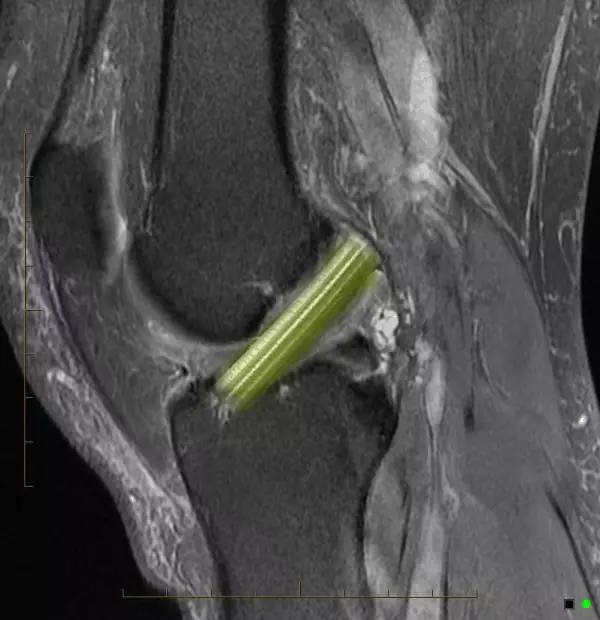

芹菜杆征是膝关节前交叉韧带黏液样变性的特征性影像表现。当前交叉韧带增粗肿大,有一定紧张度,在质子加权和T2WI的矢状位上表现为边界模糊呈高信号改变,而前交叉韧带纤维束则呈低信号条状影散布于高信号区内,形成类似芹菜杆的一种征象。

正常前交叉韧带(ACL)是由胶原纤维组成的,并在磁共振成像表现为低信号带。芹菜杆征(celery stalk sign)为ACL黏液样变性的特征性表现。关节镜下所见黏液样变性为淡黄色硬化物质,当ACL黏液样变性时,无定形的黏液细胞增加ACL的信号强度,并局部地分布于完整的、平行走行的ACL纤维束,形成了芹菜杆样外观。